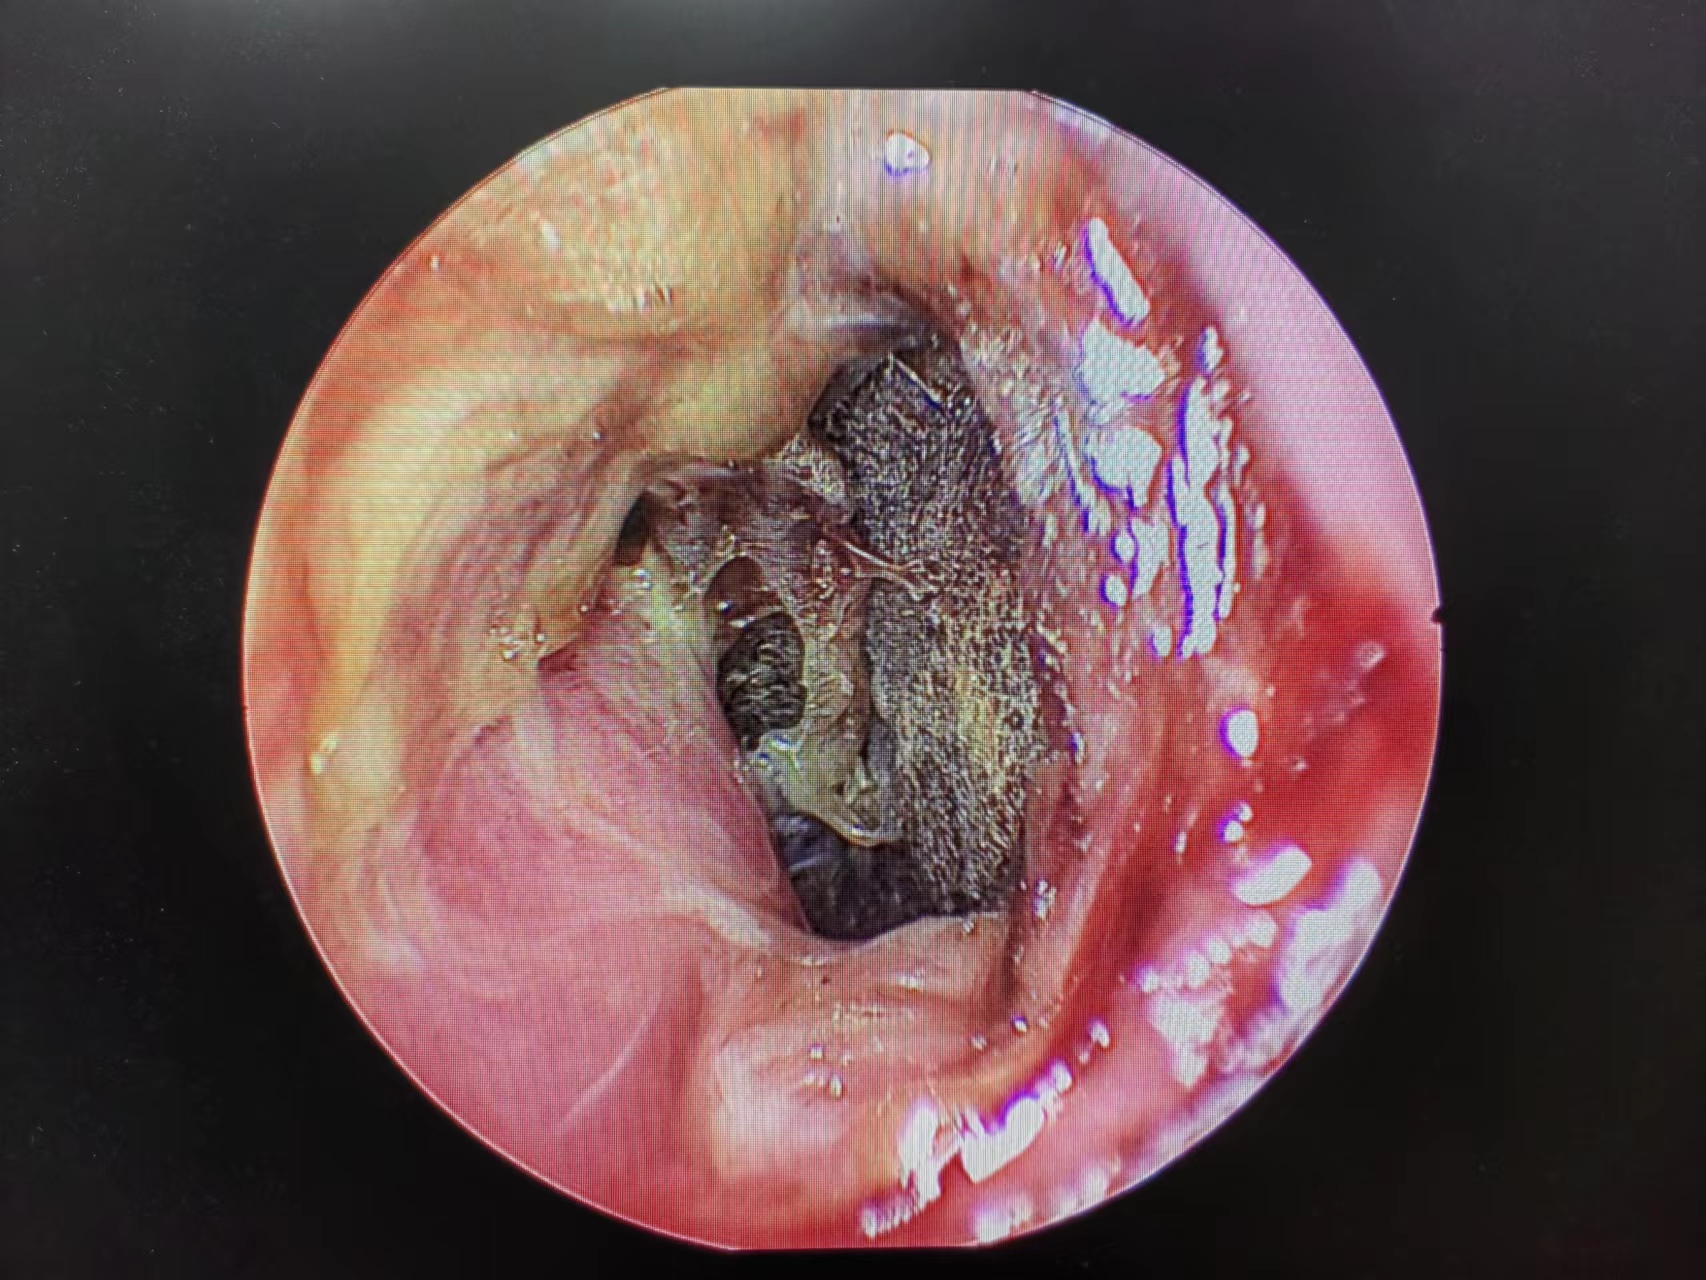

患者男,52岁,因“头痛8 d,视力下降5 d”2021年8月24日入住本院耳鼻喉科。患者8 d前受凉后出现头痛,伴双侧鼻塞和嗅觉减退,无涕中带血,无鼻腔异味,无眶周肿痛,无视力下降,自行口服头孢类抗生素治疗3 d,头痛较前减轻。5 d前出现眼周胀痛、红肿,视力下降,就诊眼科及耳鼻喉门诊,行颅脑MR检查:鼻窦炎。眼眶CT:左眶内炎症。给予抗炎治疗3 d,无效。既往史:糖尿病病史10余年,未治疗,平素未检测血糖。查体:体温36.1 ℃,脉搏64次/min,呼吸频率16次/min,血压130/81 mmHg,神志清,左眼突出,视物不见,左侧上睑下垂,眼球各方位运动受限,球结膜充血(+++)、结膜下出血(++),球结膜呈紫红色表现,全角膜白色浑浊,余眼内结构无法窥见。右眼查体未见异常。鼻外形正常,鼻根部皮肤充血(见图 1)。辅助检查:电子鼻咽镜示左侧鼻腔内大量干痂附着,予以清理后见部分痂皮与下鼻甲组织黏连紧密,中鼻道见少许菌丝样物质,少许白色分泌物流出,局部见质软肉芽组织,左侧中鼻道、嗅裂未窥及,鼻中隔略右偏,右侧鼻腔未见明显新生物(见图 2)。

| 电子鼻咽镜:左侧鼻腔内大量干痂附着,中鼻道见少许菌丝样物质,局部见质软肉芽组织 图 2 患者8月24日鼻咽镜检查结果 |